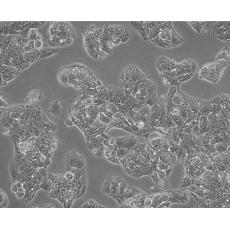

Hep G2

中文名稱 人肝癌細胞

組織來源 liver

細胞種屬 Homo sapiens, human

生長特性 adherent

形態(tài)特征 epithelial

細胞描述 該細胞來源于一名15歲的白人少年的肝癌組織。該細胞表達甲胎蛋白、白蛋白、α-2-巨球蛋白、α-1-抗胰蛋白酶、轉(zhuǎn)鐵蛋白、α-1-抗凝乳蛋白酶、結(jié)合珠蛋白、銅藍蛋白、纖溶酶原、補體C4、C3激活物、纖維蛋白原、α-1酸性糖蛋白、α-2-HS-糖蛋白、β-脂蛋白、視黃醇結(jié)合蛋白;表達胰島素受體和胰島素樣生長因子IGFⅡ的受體;該細胞具有3-羥基-3-甲酰輔酶A還原酶和肝甘油三酯脂肪酶的活性。目前尚未證明該細胞中有HBV基因組。